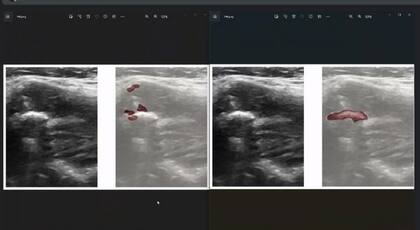

Al igual que en otras áreas de la salud, el rápido desarrollo de la inteligencia artificial encuentra aplicaciones en diversos campos, en este caso como asistencia a quienes deben realizar diagnósticos. El proyecto “Inteligencia artificial para prevenir enfermedades cardiovasculares”, una iniciativa conjunta entre la empresa Eira Healthcare e investigadores del Instituto de Investigación de Ciencias de la Salud (INICSA) de la Universidad Nacional de Córdoba y el CONICET, está desarrollando una técnica de inteligencia artificial para detectar riesgo cardiovascular en diagnóstico por imágenes. A partir del trabajo en conjunto se desarrolló un software que asiste a los médicos en la detección de arterioesclerosis cardiovascular en el análisis de las ecografías de carótida y cruzando información con otras variables de la consulta.

La arterioesclerosis es una afección en la que una placa formada por grasa, colesterol y calcio, entre otras sustancias, se acumula en las paredes de las arterias y con el tiempo se endurece, con lo que reduce el flujo de sangre por los vasos pudiendo generar infartos. Por eso, determinar el área total que ocupa la placa es vital para prevenir posibles problemas de salud. El software busca evitar uno de los limitantes más importantes de la técnica de diagnóstico, que es la variabilidad de los resultados obtenidos a partir de las imágenes, que dependen del técnico operador del ecógrafo, y así ayudar en la detección temprana y en el monitoreo de factores de riesgo.

El desarrollo ya está en su etapa final de entrenamiento del algoritmo y pronto presentará resultados preliminares. Gilda Romero es la responsable del proyecto por parte de la Fundación Sadosky: “Se le están haciendo estudios a pacientes que tienen determinadas características de historia clínica y el médico le va marcando cosas al sistema para que el algoritmo pueda reconocer esas imágenes. Esto permitirá tener una identificación más certera del riesgo que dependa menos de la experiencia de quien maneja el ecógrafo”.

Las tres etapas del proyecto

El proyecto tuvo una primera etapa en la que se desarrolló el software, una segunda etapa en la que se cargaron imágenes para entrenar al modelo en las diversas formas en que se toman imágenes por parte de diferentes operadores de ecógrafo, y una tercera en la que se cargan en forma masiva las imágenes para que la inteligencia artificial pueda determinar el riesgo cardiovascular. Se trata de una técnica novedosa y se espera que facilite el diagnóstico de estas afecciones.